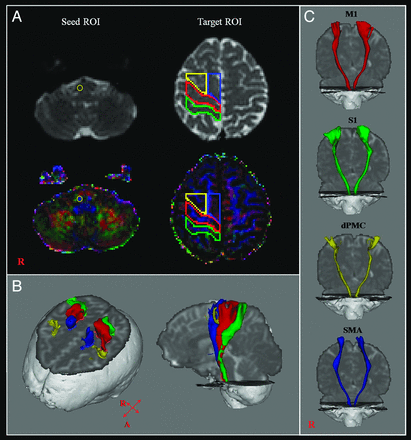

CSTs for the M1, the primary somatosensory cortex, dorsal premotor cortex, and supplementary motor area were determined by selection of fibers passing through seed and target ROIs. Seed ROIs were placed at the CST portion of the pontomedullary junction on the color map. Placement of target ROIs was as follows: 1) the primary motor cortex (anterior boundary: precentral sulcus; posterior boundary: central sulcus; medial boundary: the midline between the right and left hemispheres; lateral boundary: the line passing through the lateral margin of the precentral knob and horizontal to the midline); 2) the primary somatosensory cortex (anterior boundary: central sulcus; posterior boundary: postcentral sulcus; medial boundary: the midline between the right and left hemispheres; lateral boundary: the line passing through the lateral margin of the precentral knob and horizontal to the midline between the right and left hemispheres); 3) the dorsal premotor cortex (anterior boundary: the line joining the anterior extent of the SMA; posterior boundary: precentral sulcus; medial boundary: the lateral margin of the SMA; lateral boundary: the line passing through the lateral margin of the precentral knob and horizontal to the midline); 4) the supplementary motor area (anterior boundary: the line drawn through the anterior commissure perpendicular to the anterior/posterior commissure line; posterior boundary: anterior margin of M1; medial boundary: midline between the right and left hemispheres; lateral boundary: the line 10.6% lateral from the midline, the ratio of 15 mm to the maximum width of the Montreal Neurological Institute atlas) (Fig 1).9,28,29 Of 5000 samples generated from each seed voxel, results for each contact were visualized thresholds and weightings of tract probability at a minimum of 1 streamline through each voxel for analysis. Values of fractional anisotropy, mean diffusivity, and tract volume of the CSTs were measured.

A, The seed ROI was placed on the pontomedullary junction (CST area). Target ROIs were placed on the primary motor cortex (red), the primary somatosensory cortex (green), the dorsal premotor cortex (yellow), and the supplementary motor area (blue). B, CSTs were reconstructed in both hemispheres. Red indicates CSTs for the primary motor cortex; green, CSTs for the primary somatosensory cortex; yellow, CSTs for the dorsal premotor cortex; blue, CSTs for the supplementary motor area. C, CSTs from each ROI were reconstructed in both hemispheres.